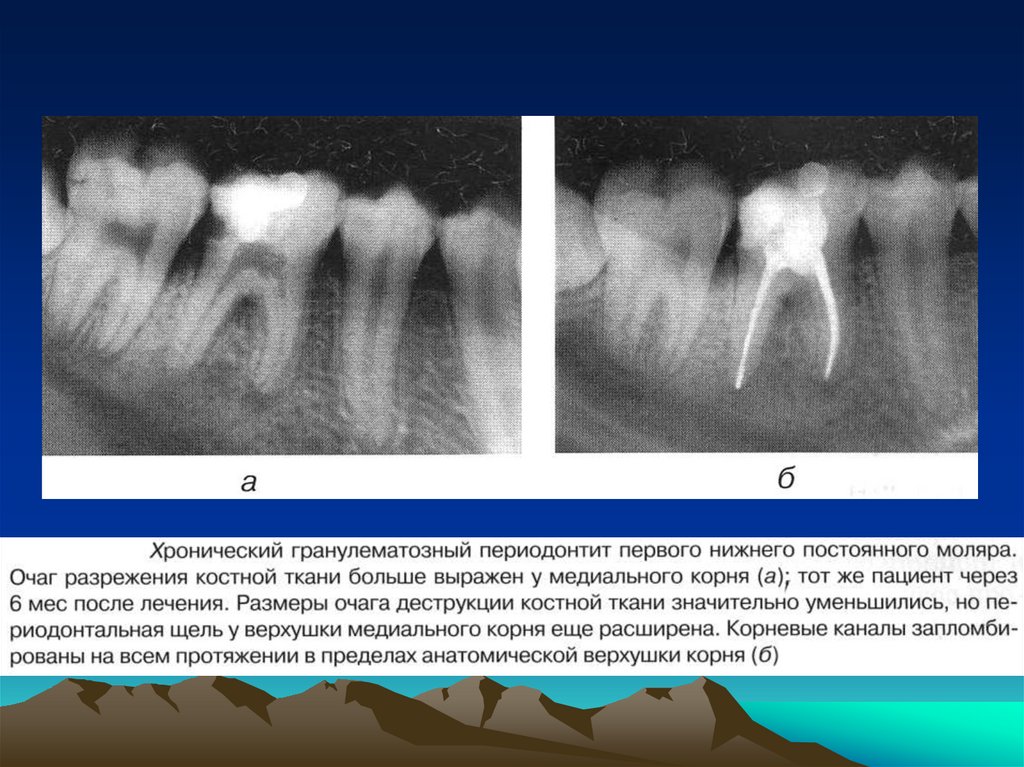

соматического

и